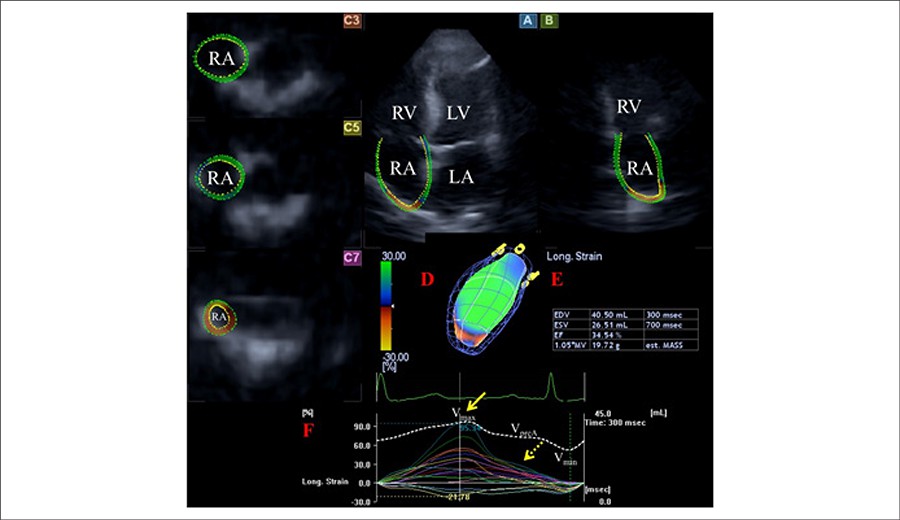

Right Atrial Deformation Analysis in Cardiac Amyloidosis – Results from the Three-Dimensional Speckle-Tracking Echocardiographic MAGYAR-Path Study

To characterize the volumetric and functional properties of the right atrium (RA) in AL-CA by three-dimensional speckle-tracking echocardiography (3DSTE).

A total of 16 patients (mean age: 64.5 ± 10.1 years, 11 males) with AL-CA were examined. Their results were compared to that of 15 age- and gender-matched healthy controls (mean age: 58.9 ± 6.9 years, 8 males). All cases have undergone complete two-dimensional Doppler and 3DSTE. A two-tailed p value of less than 0.05 was considered statistically significant.

Significant differences could be demonstrated in RA volumes respecting cardiac cycle. Total (19.2 ± 9.3% vs. 27.9 ± 10.7%, p = 0.02) and active atrial emptying fractions (12.1 ± 8.1 vs. 18.6 ± 9.8%, p = 0.05) were significantly decreased in AL-CA patients. Peak global (16.7 ± 10.3% vs. 31.2 ± 19.4%, p = 0.01) and mean segmental (24.3 ± 11.1% vs. 38.6 ± 17.6%, p =0.01) RA area strains, together with some circumferential, longitudinal and segmental area strain parameters, proved to be reduced in patients with AL-CA. Global longitudinal (4.0 ± 5.2% vs. 8.2 ± 5.5%, p = 0.02) and area (7.8 ± 8.1% vs. 15.9 ± 10.3%, p = 0.03) strains at atrial contraction and some circumferential and area strain parameters at atrial contraction were reduced in AL-CA patients.

Significantly increased RA volumes and deteriorated RA functions could be demonstrated in AL-CA.